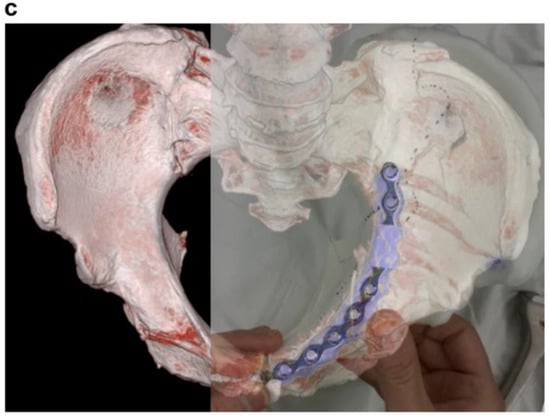

- Utilized for personalized presurgical and treatment planning. Numerous studies have showcased the potential benefits of patient-specific presurgical planning [61,62,63,64,65,66]. Additionally, it allows the customization of prosthetics or surgical tools based on individual patient anatomy, enhancing the understanding of unique and complex anatomical structures in each case [64,65,66,67]. Moreover, 3D printing permits the accurate selection of prosthetic component sizes before implantation [68,69,70].

- Sakong, S.-Y.; Cho, J.-W.; Kim, B.-S.; Park, S.-J.; Lim, E.-J.; Oh, J.-K. The Clinical Efficacy of Contouring Periarticular Plates on a 3D Printed Bone Model. J. Pers. Med. 2023, 13, 1145. [Google Scholar] [CrossRef]